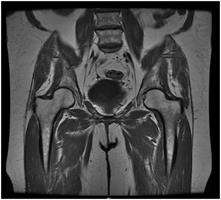

MRI of the Pelvis OB/GYN: Exam Description

Your doctor has ordered a MRI (Magnetic Resonance Imaging) of your pelvis. MRI uses a magnetic field, radio waves and a computer to create images soft tissues, bones, and internal body structures. MRI of the pelvis allows physicians to examine the pelvic anatomy to rule out any structural abnormalities.